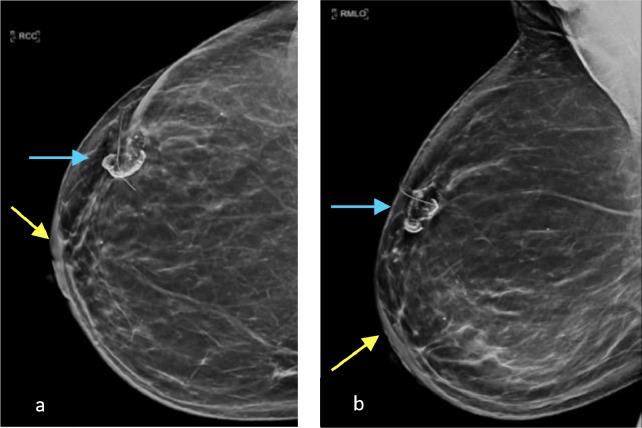

Adenoid cystic carcinoma is a rare form of breast cancer accounting for 0.1%-1.0% of all mammary malignancies. It is characterized by an indolent clinical course and favorable prognosis, contrary to other breast cancers. Diagnostic mammogram and breast ultrasound play a pivotal role in the early detection and diagnosis of breast adenoid cystic carcinoma. Treatment may consist of lumpectomy and radiation therapy vs mastectomy alone. Even though rare, late disease recurrence and metastasis has been reported in the literature thus long-term surveillance is of utmost importance for these patients. We will review the literature and discuss the case of a 52-year-old female who presented with a palpable lump of the right breast, which was pathologically proven to be adenoid cystic carcinoma of the breast.

腺样囊性癌是一种罕见的乳腺癌类型,占所有乳腺恶性肿瘤的0.1%-1.0%。与其他乳腺癌不同,其临床病程进展缓慢,预后良好。诊断性乳房X光检查和乳房超声在乳腺腺样囊性癌的早期检测和诊断中起着关键作用。治疗方法包括肿块切除术加放射治疗或单纯乳房切除术。尽管罕见,但文献中已有晚期疾病复发和转移的报道,因此对这些患者进行长期监测至关重要。我们将回顾相关文献,并讨论一名52岁女性的病例,该患者右乳出现可触及肿块,病理证实为乳腺腺样囊性癌。